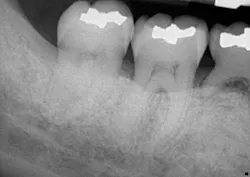

A clinical periodontal and radiographic assessment is completed. Although there is moderate bone loss in all four quadrants, his periodontal status is stable with the exceptions of Nos. 18 and 31 distal (figures 1 and 2). Both areas reveal direct distal probing depths of at least 10 mm and radiographic infrabony distal defects.

Figure 2: No. 31